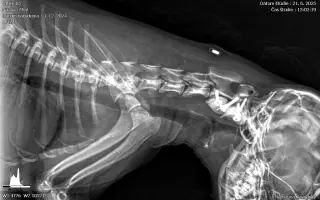

Od operácie ubehli už 2 mesiace a Mini podstúpila tento týždeň kontrolný röntgen. Po konzultácii kontrolného röntgenu s veterinárom môžeme s Mini postupne začať zvyšovať pohybovú aktivitu a predlžovať prechádzky, čo pre nás znamená, že sa budeme môcť pomaličky začať opäť hrať a chodiť von na dlhšie ako len na 5 minút.

Spolu sme navštívili množstvo vyšetrení, až kým mi nezistili závažnú diagnózu – nestabilita atlanto-axiálneho (C1-C2) spojenia. Operáciu som mala absolvovať 30. 7. 2025. No môj stav sa 13. 7. nečakane zhoršil – moje nožičky prestali poslúchať a ja som sa nevedela ani sama vycikať. Skúšala som, naozaj som sa snažila, ale už to nešlo…